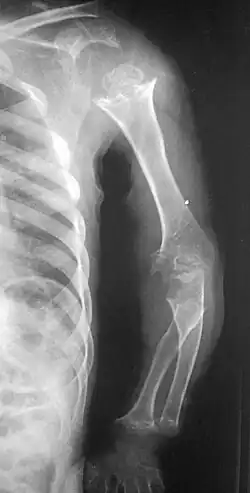

| Pseudoachondroplasia. Shoulder and humerus. Note the dysplastic proximal humeral epiphysis, metaphyseal broadening, irregularity and metaphyseal line of ossification. These changes are collectively known as "rachitic-like changes". Lesions are bilateral and symmetrical. | |

- Dysplastic/hypoplastic epiphyses especially of shoulders and around the knees.

- Metaphyseal broadening, irregularity and metaphyseal line of ossification. These abnormalities that are typically encountered in proximal humerus and around the knees are collectively known as "rachitic-like changes".

- Radiographic lesions of the appendicular skeleton are typically bilateral and symmetric.